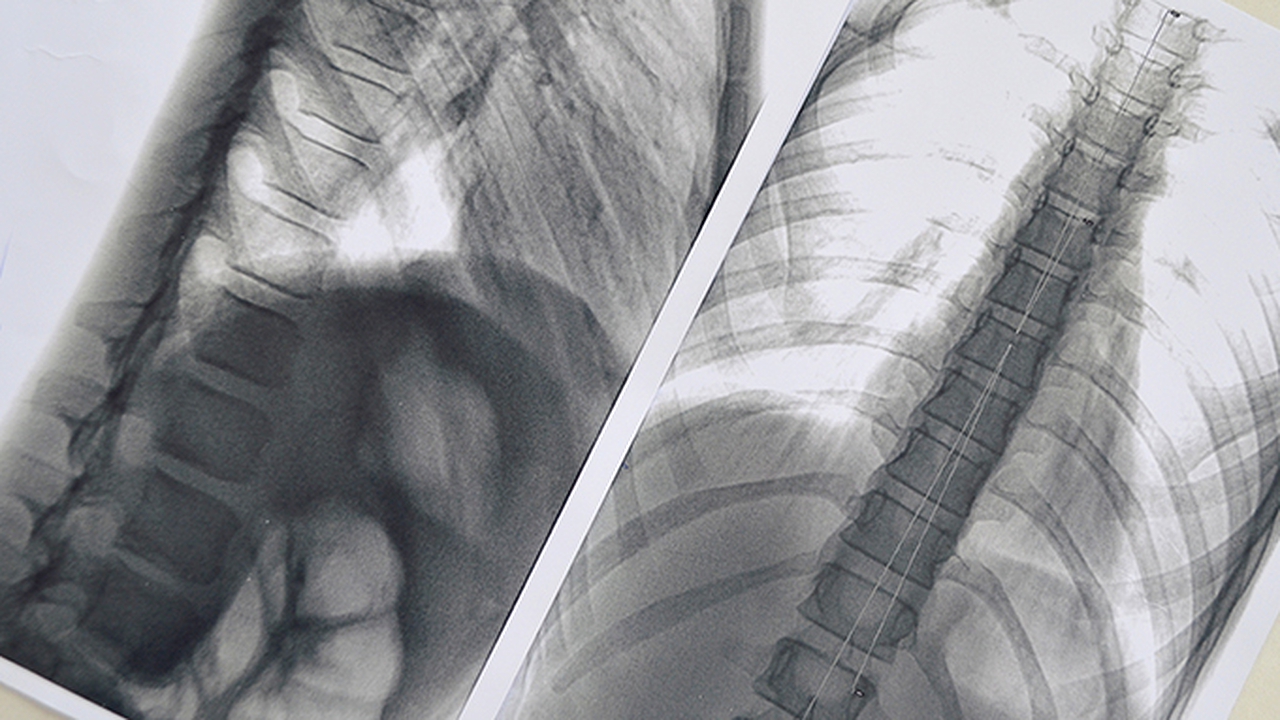

肺结节多为肺部影像学检查发现的异常阴影,可能与感染、炎症或肿瘤相关。早期明确诊断对制定治疗方案至关重要,需结合影像特征、病史及病理检查综合判断。